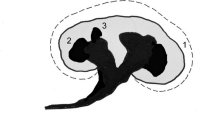

Die Refluxnephropathie ist von einer fortschreitenden Destruktion des Nierenparenchyms geprägt (Abbildung 7). Die pathologischen Veränderungen sind dabei abhängig vom Grad des Refluxes und oder der bakteriellen Infektion.

Die Nieren sind klein und haben ein Gewicht von ca. 40g. Die Nierenoberfläche ist diffus-höckrig. Refluxnarben finden sich an den Polen und der Mitte des Organs. Auf der Schnittfläche zeigt sich das Parenchym reduziert, z.T. mit abgeflachten Papillen und Bildung von Exkavationen bzw. Rezessi (Abbildung 7,8,9)